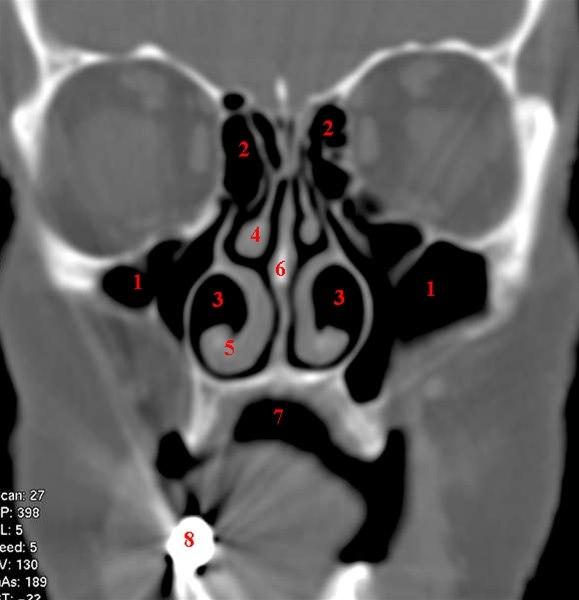

CT-snitt i coronalplan gjennom fremre del av maxillarsinus

- Sinus maxillaris

- Sinus etmoidales

- Cavum nasi

- Conchae medius

- Conchae inferior

- Septum nasi

- Cavum oris

- Tannfylling som gir stripeartefakter i bildet